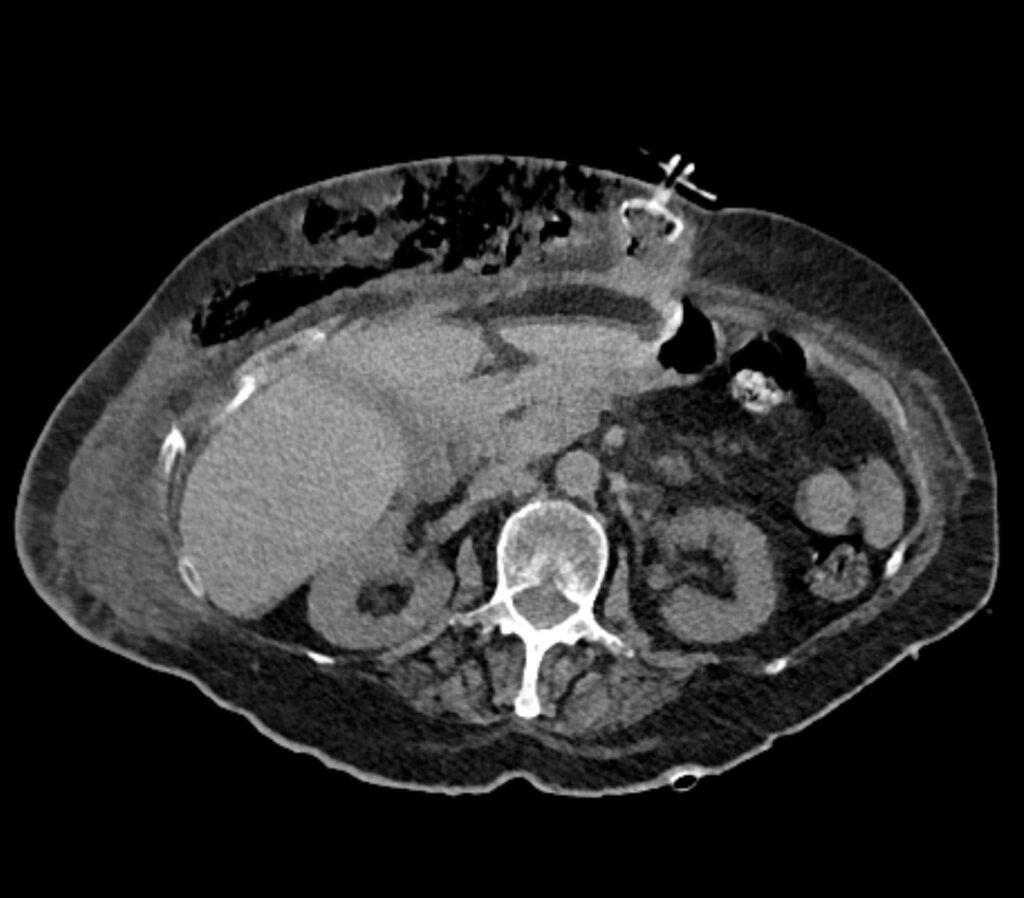

*73-year-old female presented with fever and epigastric redness.

What is the most likely diagnosis?

Answer:

Dislodgement of the PEG tube

CT image revealed dislodgement of the internal bumper of the PEG tube and subcutaneous collection of fluid and air in the abdominal wall.